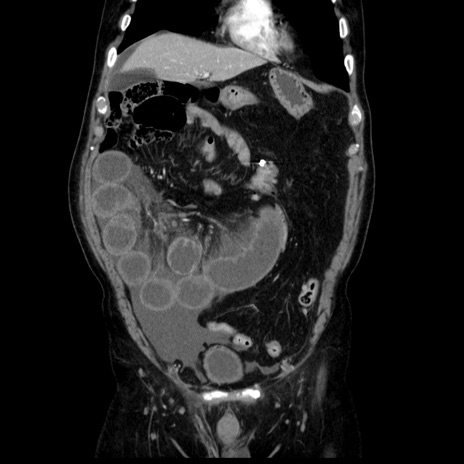

症例30(冠状断像)

【症例】80歳代男性

【主訴】臍周囲痛

【現病歴】約6時間前から臍下部痛が出現。次第に腹部膨隆・背部痛も生じてきたため来院。背部痛の場所は変化しない。

【既往歴】腎盂腎炎

【身体所見】意識清明、BT 36.3℃、BP  131/87mmHg、P 87bpm、SpO2 100%(RA)、臍周囲自発痛・圧痛あり、反跳痛なし、自発痛部位に一致して板状硬あり、腹部膨隆、腸雑音減弱、CVA tenderness両側陰性。

【データ】WBC 19600、CRP 0.33